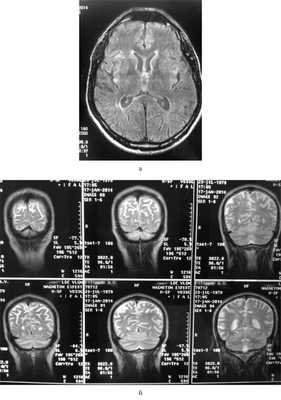

На МРТ головного мозга в режиме DWI были определены аномальные билатеральные гиперинтенсивные сигналы на Т2-взвешенных изображениях, преимущественно в области головок хвостатых ядер, таламуса, атрофия коры больших полушарий (рис. 1). Рис. 1. Билатеральные гиперинтенсивные сигналы в области подкорковых ганглиев на Т2-взвешенных изображениях МРТ головного мозга (а) и атрофия коры головного мозга на МРТ головного мозга на первом году заболевания.

На диффузионно-взвешенной (DWI) магнитно-резонансной томографии (МРТ) головного мозга выявляются аномальные билатеральные гиперинтенсивные сигналы на Т2-взвешенных изображениях (симптом «медовых сот») преимущественно в области головок хвостатых ядер, таламуса, отмечается атрофия коры больших полушарий и мозжечка [6].

При проведении МРТ головного мозга в Т2-режиме определяется так называемый «симптом медовых сот» - участки повышенного сигнала, исходящие от подкорковых ганглиев и таламуса. Зачастую выявляются признаки атрофических изменений мозжечка и коры головного мозга, расширение желудочков и боковых цистерн мозга. ПЭТ диагностирует зоны пониженного метаболизма, локализующиеся в подкорковых ядрах, полушариях мозжечка и коре мозга.